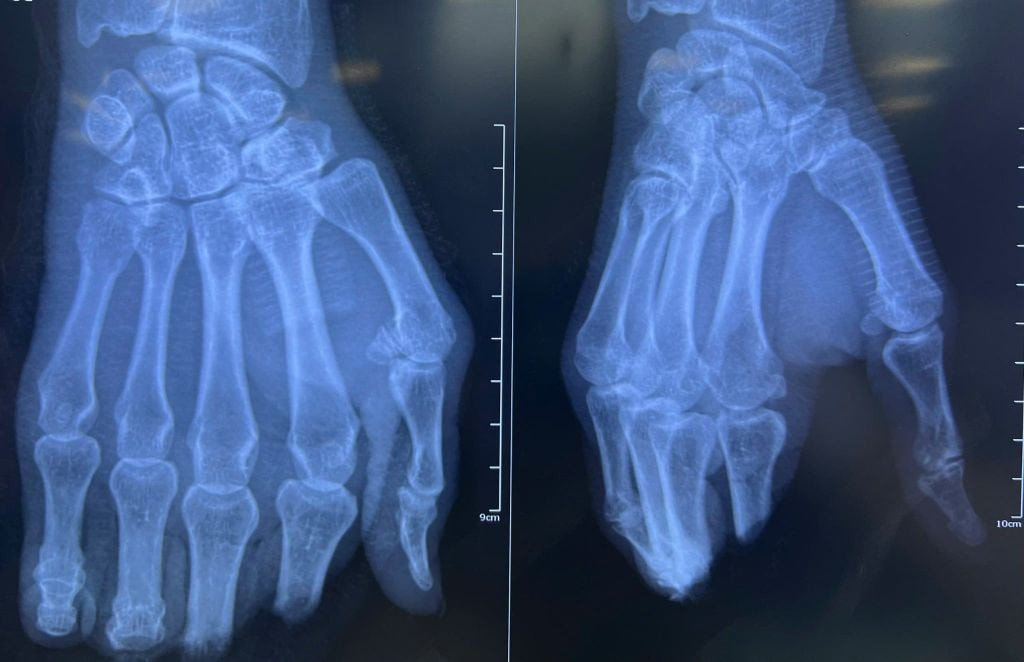

Theo đó, ông Q. nhập viện vào chiều 16/3 trong tình trạng đứt lìa hoàn toàn các ngón II, III, IV và V bàn tay phải. Qua thăm khám, các bác sĩ xác định đây là ca bệnh có mức độ phức tạp cao khi vị trí đứt nằm tại khớp liên đốt gần và đốt xa, kèm theo mô mềm bị dập nát nghiêm trọng.

Quá trình phẫu thuật gặp nhiều trở ngại do mạch máu đầu xa rất nhỏ và bị dập nát nhiều, đòi hỏi sự tỉ mỉ và chính xác tuyệt đối trong từng thao tác để bảo tồn thành công các mạch máu. Các bác sĩ lần lượt thực hiện cố định xương, nối mạch máu, nối thần kinh, nối gân gấp và gân duỗi cho từng ngón tay.